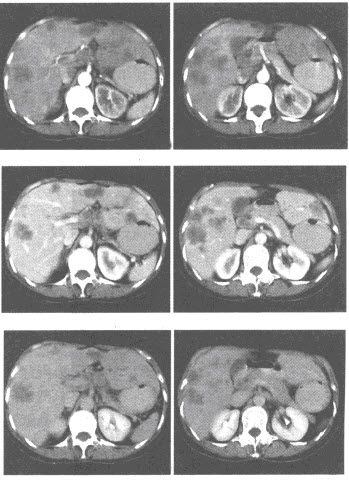

(多选题)关于动脉瘤样骨囊肿的表现描述正确的是()

A:各年龄段均可发病,好发于长骨干骺端

B:在X线平片上病灶为显著膨胀的囊状透亮区,可位于骨干的中央,不能偏心生长

C:CT及MRI上可见液-液平面

D:病灶主要由大小不等海绵状血池组成,分为原发性和继发性两种

E:是肿瘤样病变,而非真正意义上的肿瘤